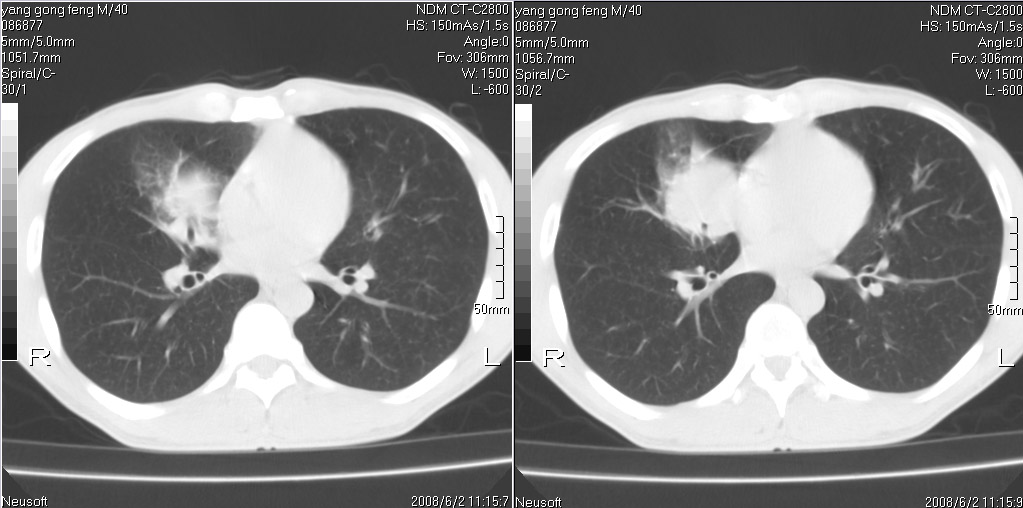

标题: CT15138:男,40,咳嗽胸痛. [打印本页]

标题: CT15138:男,40,咳嗽胸痛.

外院穿刺未见癌细泡,结核菌素实验阳性,未正规治疗2个月复查病灶及纵隔淋巴结增大

结合病史及临床表现考虑右侧中心型肺癌纵隔转移,

考虑周围型肺癌可能性大

右侧中心型肺癌纵隔转移!

右肺中叶肺癌,纵隔淋巴结转移.

考虑   右肺中叶肺癌,纵隔淋巴结转移.建议穿刺活检。炎性假瘤待排

考虑右肺中叶周围型肺癌并纵隔淋巴结转移。